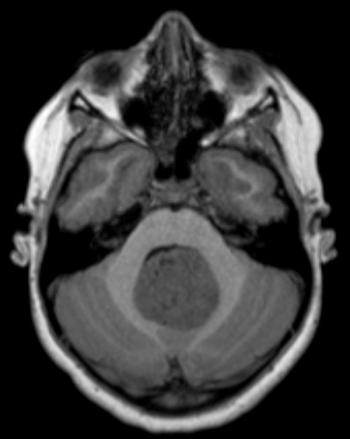

Can you diagnose this patient with dizziness?